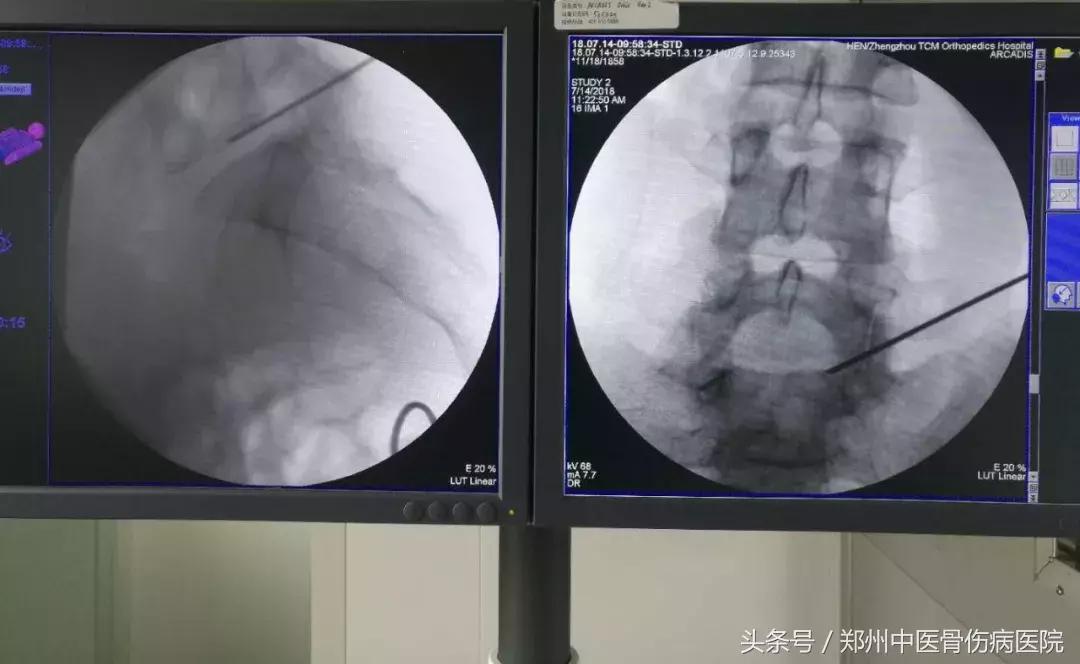

C臂定位下 穿刺到位